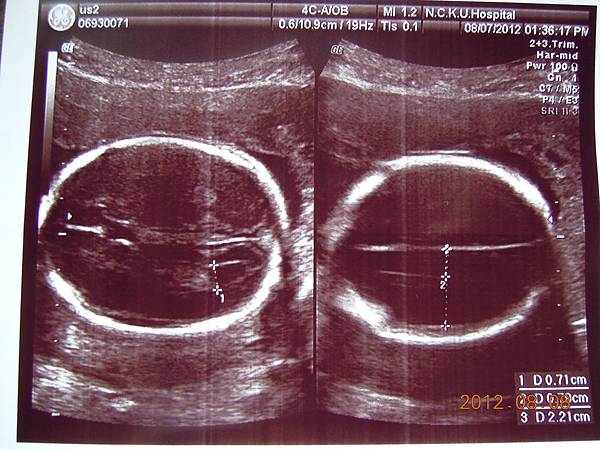

除了比較明顯的骨頭可以看的出來,其實我們看不太懂,但是他精熟的技術很快把每個部位的大小都量測出來,我躺在床上看著上頭的螢幕,慢慢欣賞他的每張超音波照片~~

可以看到的是在逼逼的上方剛好被胎盤擋著,比較看不到他的正面,除了肛門無法看到(怕沒有肛門),醫師說現在看不到,小雞雞也沒照他的大小(我怕他發育不良),其他身體器官包括腦部剖有量測他的大小及羊水多寡(我怕像上次一樣羊水太少),今天量出來是12,喔彌陀佛~~

這是他給我的報告,都是一些代號,游醫師說明很快,不過我聽他說沒問題,就比較放心,裡面有把每個器官大約生長到幾週做個說明,大致都在22~24周,逼逼體重約697g~

接下來就是他的一堆檢查照片啦~~